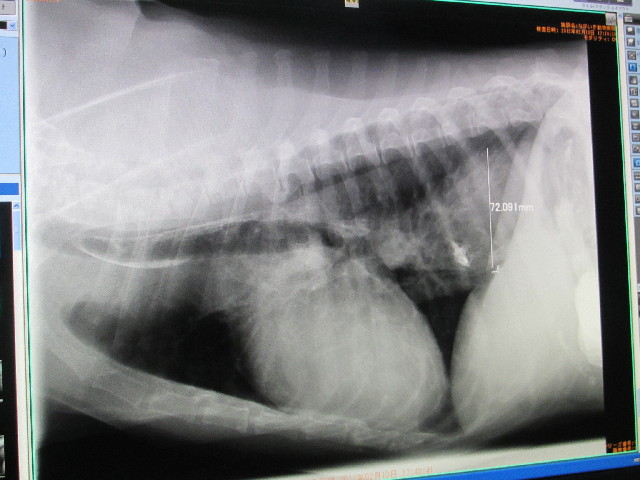

飲んだバリウムはすぐに通っているし、Qちゃんは大きくなっていないようです。

(一番大きいところが72.091mmで1月18日の77.785mmよりむしろ小さくなった?)

白く写っている所はバリウムの跡です。